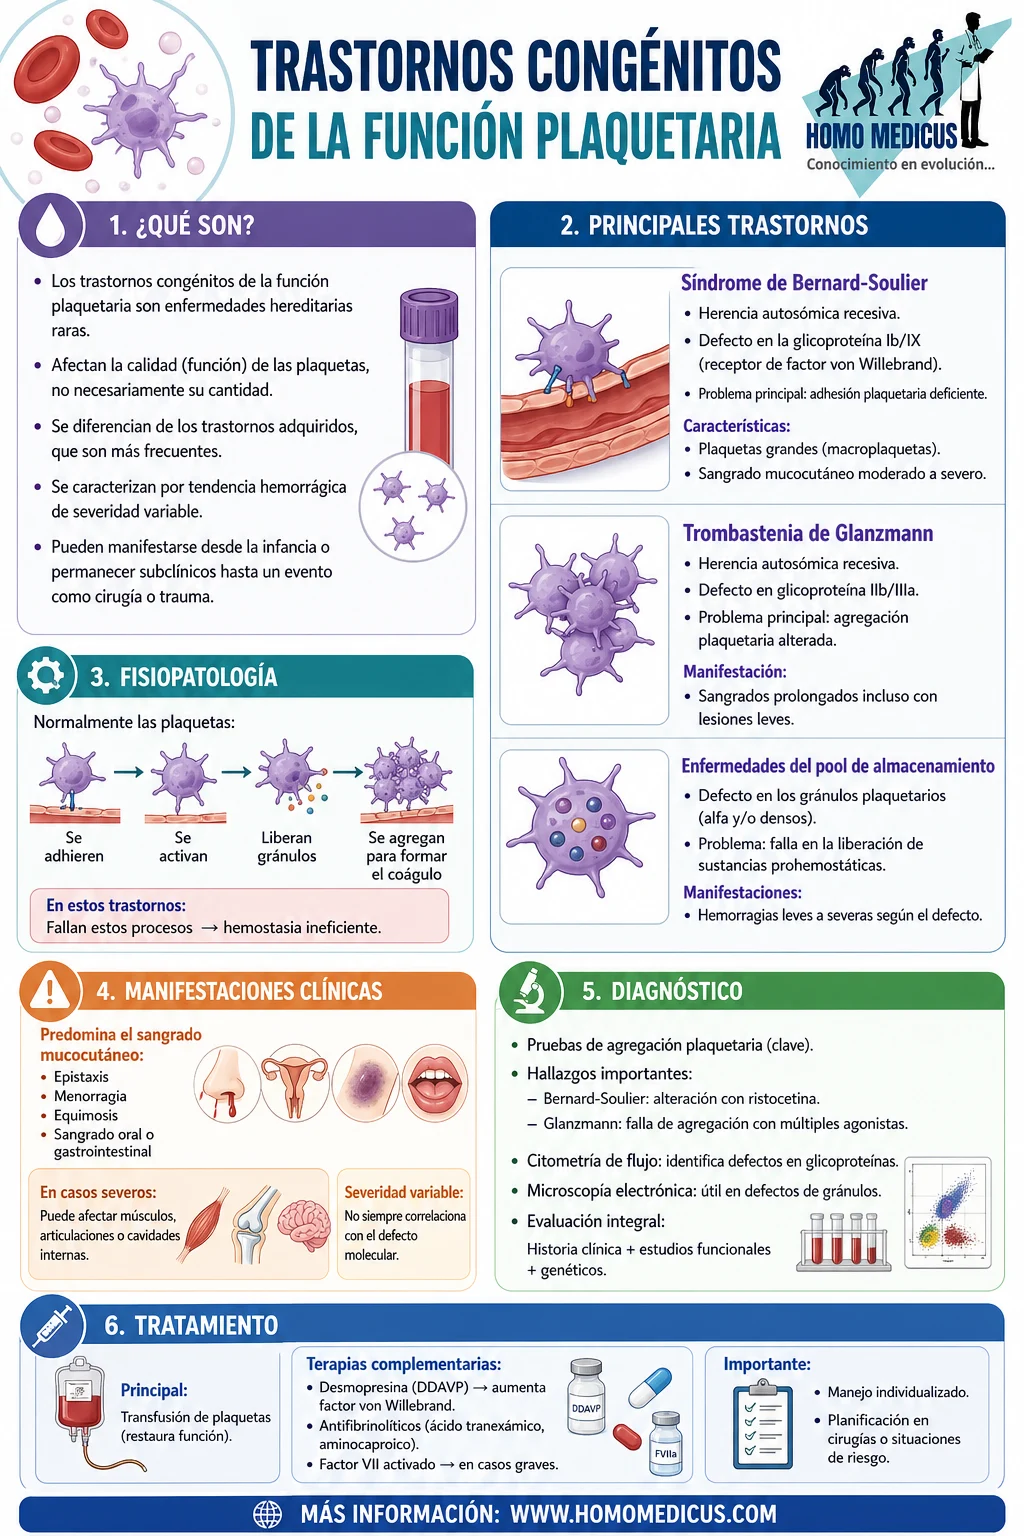

Los trastornos congénitos de la función plaquetaria representan un conjunto poco frecuente de patologías hereditarias que afectan la calidad funcional de las plaquetas, en contraste con los trastornos adquiridos de la función plaquetaria, que son más comunes. Estas afecciones se caracterizan por una tendencia hemorrágica de severidad variable, generalmente manifestándose desde la infancia. Sin embargo, en algunos casos, estos trastornos permanecen subclínicos hasta que un desafío hemostático significativo, como una cirugía o un trauma, revela la disfunción. Debido a esta presentación clínica variable y ocasionalmente tardía, la incidencia real de los trastornos cualitativos hereditarios de las plaquetas es desconocida.

- Síndrome de Bernard-Soulier (BSS):

- Es un trastorno autosómico recesivo raro que resulta de la reducción o anomalía en la expresión de la glicoproteína Ib/IX en la membrana plaquetaria, que actúa como receptor del factor de von Willebrand (vWF).

- La glicoproteína Ib/IX es esencial para la adhesión de las plaquetas al subendotelio en respuesta a una lesión vascular. Una alteración en este complejo afecta gravemente la capacidad de las plaquetas para iniciar la hemostasia primaria.

- Los pacientes presentan plaquetas de gran tamaño (macroplaquetas) y suelen experimentar sangrados mucocutáneos moderados a severos.

- Trombastenia de Glanzmann:

- Es otro trastorno autosómico recesivo, causado por una anomalía en el receptor glicoproteico IIb/IIIa en la membrana plaquetaria. Este receptor es crítico porque media la unión del fibrinógeno, esencial para la agregación plaquetaria inicial y la formación del tapón plaquetario.

- Las personas afectadas presentan defectos graves en la agregación plaquetaria, resultando en sangrados prolongados incluso con lesiones menores o procedimientos invasivos.

- Enfermedades del pool de almacenamiento:

- Incluyen un espectro de defectos que afectan la liberación de los gránulos plaquetarios alfa o densos (delta), o ambos. Estas estructuras intracelulares son fundamentales en la amplificación de la respuesta agregatoria de las plaquetas mediante la liberación de factores prohemostáticos.

- Los pacientes pueden experimentar hemorragias leves a moderadas dependiendo de la extensión del defecto. En los casos más severos, como en la enfermedad del pool alfa-delta, la disfunción es más generalizada.

Mecanismos fisiopatológicos y consecuencias clínicas

En condiciones normales, las plaquetas se activan tras la exposición a señales prohemostáticas, como el colágeno subendotelial, liberando el contenido de sus gránulos para reforzar la agregación y promover la formación del coágulo. En los trastornos cualitativos de las plaquetas, la interrupción de estos procesos resulta en una incapacidad para detener eficazmente la hemorragia. Esto puede manifestarse como sangrado espontáneo, menorragia, equimosis fácil, epistaxis persistente o complicaciones hemorrágicas tras procedimientos quirúrgicos.

La identificación temprana de estos trastornos es crucial para el manejo efectivo, que puede incluir transfusiones de plaquetas normales, terapia con desmopresina (DDAVP), o tratamiento con agentes antifibrinolíticos, dependiendo del trastorno específico y de la severidad del sangrado.

Manifestaciones clínicas

El sangrado causado por defectos en la función de las plaquetas se manifiesta, con mayor frecuencia, en las superficies mucocutáneas, como las mucosas de la boca, nariz, tracto gastrointestinal y genital, así como en la piel. Estas áreas son particularmente susceptibles debido a su alta vascularización y la necesidad de una hemostasia eficiente para mantener la integridad de los tejidos. Sin embargo, este tipo de hemorragia no se limita exclusivamente a estas regiones. En ciertos casos, especialmente en aquellos con defectos severos o en presencia de otros factores predisponentes, el sangrado puede afectar tejidos profundos como músculos, articulaciones o incluso cavidades internas.

Estos trastornos subrayan la complejidad de las enfermedades plaquetarias cualitativas. Su diagnóstico requiere una evaluación cuidadosa, que incluya pruebas específicas de función plaquetaria, estudios genéticos y un análisis detallado de los antecedentes clínicos. El tratamiento debe ser individualizado, considerando la gravedad de los síntomas y los riesgos asociados. Las intervenciones pueden incluir transfusiones de plaquetas normales, el uso de agentes antifibrinolíticos o terapias dirigidas según las necesidades del paciente. En contextos quirúrgicos o situaciones de alto riesgo hemorrágico, una planificación meticulosa es crucial para evitar complicaciones graves.

Exámenes diagnósticos

El síndrome de Bernard-Soulier es un trastorno hereditario caracterizado por anomalías en la función y morfología de las plaquetas, lo que resulta en alteraciones hemostáticas significativas. Los pacientes con esta condición presentan plaquetas anormalmente grandes, que pueden alcanzar el tamaño de los eritrocitos, y trombocitopenia moderada, lo que contribuye a un tiempo de sangrado prolongado. Estas alteraciones reflejan defectos en el complejo glicoproteico Ib/IX/V, un receptor esencial para la unión del factor de von Willebrand y la adhesión inicial de las plaquetas al subendotelio tras una lesión vascular.

Los estudios de agregación plaquetaria son clave en la evaluación diagnóstica del síndrome de Bernard-Soulier. En estos pacientes, la respuesta a ristocetina, un agonista que depende de la funcionalidad del complejo glicoproteico Ib/IX/V, está severamente afectada, lo que se traduce en un defecto notable en la agregación. Sin embargo, la respuesta a otros agonistas, como ADP o colágeno, permanece normal, lo que indica que las vías de activación intracelular no están comprometidas. Al añadir plaquetas normales a la muestra del paciente, se corrige la agregación anómala, confirmando que el defecto es intrínseco a las plaquetas del individuo afectado. El diagnóstico definitivo puede establecerse mediante citometría de flujo, que permite cuantificar la expresión anormal o ausente del complejo glicoproteico en la membrana plaquetaria.

En la trombastenia de Glanzmann, el defecto reside en la glicoproteína IIb/IIIa, que actúa como receptor para el fibrinógeno, una proteína clave en la formación del tapón plaquetario. Los estudios de agregación plaquetaria en estos pacientes revelan una marcada alteración en la agregación en respuesta a diversos agonistas, como ADP, trombina o colágeno, reflejando la incapacidad de las plaquetas para formar enlaces efectivos entre sí. Este defecto ilustra el papel crítico del receptor de fibrinógeno en la hemostasia primaria y destaca la gravedad del compromiso funcional en esta enfermedad.

Por otro lado, la enfermedad del pool de almacenamiento abarca un conjunto heterogéneo de defectos que afectan la cantidad, contenido o funcionalidad de los gránulos alfa o densos de las plaquetas, o ambos. Estas estructuras intracelulares son fundamentales para la amplificación de la respuesta hemostática, ya que contienen factores procoagulantes y moduladores esenciales para la agregación plaquetaria y la estabilización del coágulo. Dependiendo de la naturaleza del defecto, los pacientes pueden experimentar una amplia gama de manifestaciones hemorrágicas, desde episodios leves hasta sangrados espontáneos graves.

Tratamiento

El tratamiento principal para los trastornos de la función plaquetaria, incluyendo la profilaxis en procedimientos invasivos, consiste en la transfusión de plaquetas normales. Este enfoque es fundamental debido a que las plaquetas transfundidas no solo reemplazan las plaquetas disfuncionales del paciente, sino que también restablecen temporalmente la capacidad de formar un tapón plaquetario funcional en respuesta a lesiones vasculares. Esto es particularmente crucial en contextos donde se anticipa un desafío significativo al sistema hemostático, como cirugías, partos o traumas.

La transfusión de plaquetas es eficaz porque introduce plaquetas funcionales que pueden participar adecuadamente en las etapas iniciales de la hemostasia primaria. Estas plaquetas normales interactúan con los receptores y factores del sistema hemostático del paciente, asegurando una adhesión, activación y agregación eficaces. En trastornos graves como el síndrome de Bernard-Soulier o la trombastenia de Glanzmann, donde las plaquetas del paciente son incapaces de cumplir estas funciones de manera adecuada, las plaquetas transfundidas ofrecen un soporte hemostático directo y eficiente.

Además de la transfusión de plaquetas, se utilizan otros tratamientos complementarios en situaciones específicas para potenciar la respuesta hemostática. Entre estos se incluye el acetato de desmopresina, un análogo sintético de la hormona antidiurética que estimula la liberación del factor de von Willebrand y del factor VIII desde los reservorios endoteliales. Esto es útil en pacientes con trastornos donde estos factores juegan un papel crítico en la estabilización del coágulo, aunque su eficacia puede ser limitada en trastornos estrictamente relacionados con la función plaquetaria.

Los agentes antifibrinolíticos, como el ácido tranexámico o el ácido épsilon-aminocaproico, son igualmente valiosos en ciertas situaciones clínicas. Estos medicamentos actúan inhibiendo la degradación prematura del coágulo por parte de las enzimas fibrinolíticas, lo que prolonga la estabilidad del tapón hemostático y reduce el riesgo de hemorragias recurrentes. Son especialmente útiles como terapia adyuvante en procedimientos quirúrgicos, lesiones traumáticas o en situaciones donde se espera un riesgo elevado de sangrado mucoso.

El factor VII humano activado recombinante representa otra herramienta terapéutica para el manejo de episodios hemorrágicos graves o refractarios en pacientes con trastornos de la función plaquetaria. Este agente actúa promoviendo la generación local de trombina, lo que acelera la formación de fibrina y ayuda a compensar las deficiencias en la formación del tapón plaquetario. Aunque su uso es generalmente reservado para casos extremos debido a su elevado costo y potencial riesgo trombótico, puede ser decisivo en situaciones de hemorragias incontrolables.